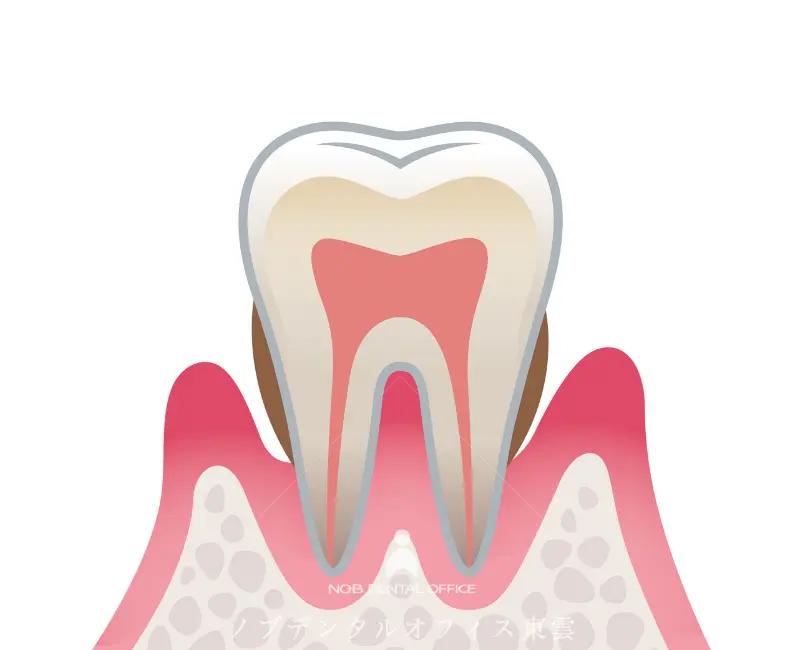

健康な歯ぐき

健康な歯ぐきは引き締まり、ピンク色で、歯にしっかりと付いています。

腫れや出血はなく、歯を支える骨もしっかり保たれています。